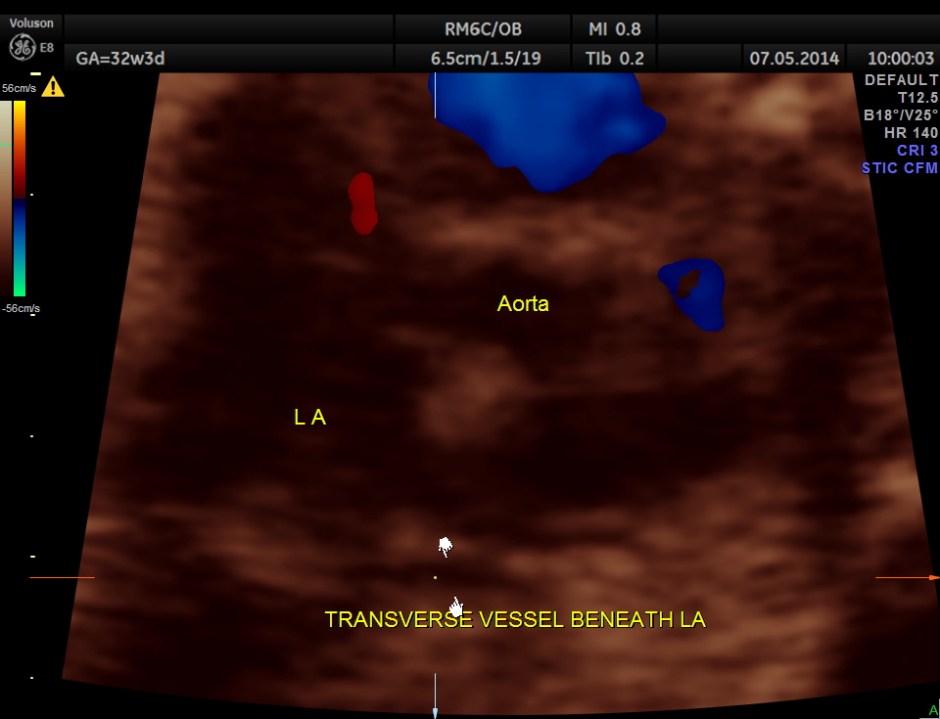

The following is a glass body imaging with a low flow setting. No pulmonary vein draining into LA could be made out.

A transverse vessel is seen below the left atrium and is not seen to drain into the left atrium.

No definitive pulmonary vein draining into the left atrium could be made out . A common transverse vessel was seen beneath the left atrium . The LA & RA were smaller than the RA. Similarly the Aorta and the aortic arch were smaller than the pulmonary artery and the ductal arch due to the increased flow in the right side.